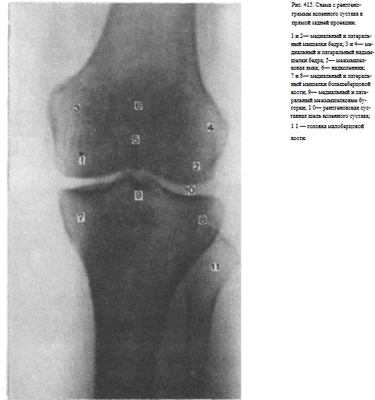

Информативность снимка. На снимке коленного сустава в прямой задней проекции определяются дистальный метаэпифиз бедренной кости, медиальный и латеральный мыщелки бедра, между которыми располагается межмыщелковая ямка. Выше мыщелков определяются медиаль-ный и латеральный надмыщелки. На фоне дистального метаэпифиза бедренной кости виден надколенник. Проксимальный эпифиз большеберцовой кости представлен медиальным и латеральным мыщелками, между

которыми определяются медиальный и латеральный межмыщелковые бугорки. На латеральный отдел метаэпифиза большеберцовой кости частично накладывается головка малоберцовой кости. Между мыщелками бедренной и большеберцовой костей выявляется рентгеновская суставная щель коленного сустава в виде неравномерно изогнутой полосы просветления (рис. 415).